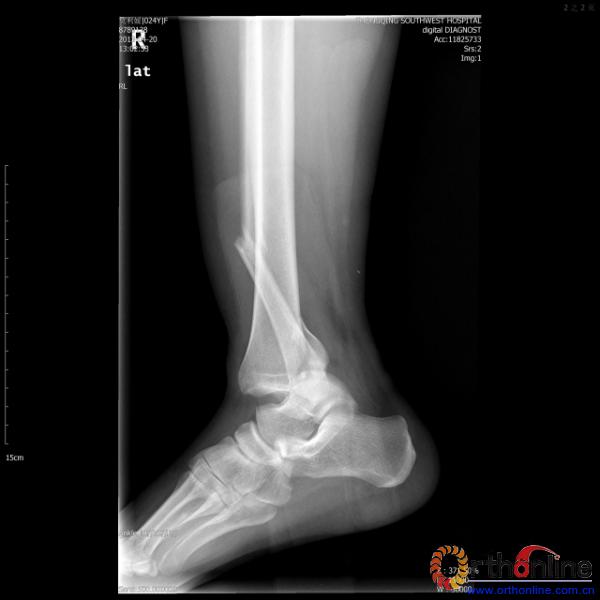

2013年4月20日 8:02分四川雅安芦山县发生7.0级地震后,重庆市有震感,24岁的莫老师在赶往上班的途中突遇此事,导致右踝关节畸形,不能站立和行走。

伤员和家属迅速赶到西南医院,10点关节外科段小军副教授查看伤员后急诊收入院,拍摄X片和急诊行三维CT重建检查,提示踝关节创伤严重,出现三踝骨折伴胫距关节脱位,需要急诊手术治疗。随后段教授与正在四川成都参加“汶川地震5周年灾害医学救治研讨会”的杨柳主任联系,进一步完善救治方案。地震当晚,段教授为该伤员进行急诊手术,手术顺利对复杂骨折进行了解剖复位,有效的钢板螺钉固定。术后伤员的疼痛明显缓解,复查X片,踝关节结构恢复满意。

患者术前X片(二)